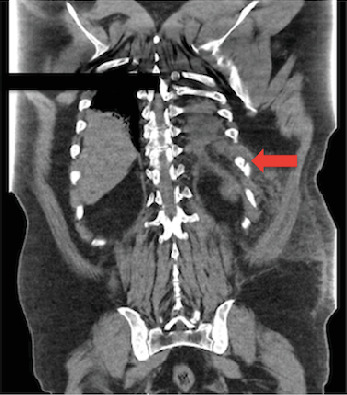

Hemothorax, the accumulation of blood in the pleural space, is most frequently linked to chest trauma but can occasionally result from nontraumatic causes such as persistent or forceful coughing. Cough-induced rib fractures are rare, with an even less frequent association with hemothorax. We describe a case involving a 57-year-old male who presented with a worsening cough and left-sided pleuritic chest pain despite prior antibiotic and symptomatic treatment. Initial imaging revealed a minimally displaced 10th rib fracture, left-sided atelectasis, and trace pleural effusion. During his hospital stay, he developed acute respiratory distress and increased chest pain, with repeat imaging revealing a large left-sided hemothorax. Chest tube placement drained 1100 mL of blood, supporting the diagnosis of hemothorax, as evidenced by clinical presentation and imaging, despite the absence of fluid analysis. The patient's condition improved following the intervention, and he was discharged in stable condition without recurrence of hemothorax on follow-up imaging. This case highlights the rare association between cough-induced traumatic rib fractures and delayed development of hemothorax. While rib fractures typically result from blunt trauma, they can also occur from stress or repetitive coughing. Complications such as hemothorax are uncommon but potentially life-threatening. The interval development of hemothorax, as seen in this patient, underscores the importance of serial monitoring in cases of rib fractures with ongoing symptoms. Clinicians should maintain a high index of suspicion for hemothorax in patients presenting with rib fractures and persistent cough, particularly in the context of worsening respiratory symptoms or pleuritic chest pain. Early recognition and timely intervention are critical to optimizing outcomes and mitigating the risks of rapid clinical deterioration.